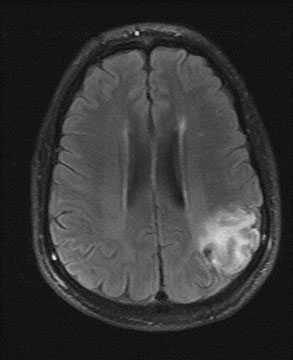

In the evaluation of extracranial large vessel disease, mainly carotid disease, ultrasound is the initial indicated study. It is commonly available, relatively inexpensive, and accurate. In addition, compared to other vascular imaging methods, it has the ability to directly image and characterize the plaque. Certain plaque characteristics may predict an increased risk of embolization. For example, the presence of an ulcer at the plaque surface may promote the formation of thrombus that can secondarily embolize, while a hypoechoic plaque, representing either intraplaque hemorrhage or a lipid-rich plaque, is associated with the potential for plaque destabilization.79,80 Carotid artery ultrasound has a sensitivity of 90% to 95% and specificity of 85% compared to catheter angiography.81 However, ultrasound may be unable to detect high-grade stenosis and mistakenly diagnose a carotid occlusion in 5% of cases. It is important to make this distinction as a patent vessel may be amenable to a revascularization procedure. Although power Doppler and echo-contrast agents may improve the odds of a correct diagnosis, for now it is standard practice to corroborate carotid occlusions with another imaging modality such as MRA, computed tomographic angiography (CTA), or conventional catheter angiography. MRA is an evolving technology comparable in accuracy to ultrasound, with the advantage of being able to image the distal carotid. In the past, there was a risk of overestimation of carotid stenosis by MRA, and beyond 70% stenosis, the absence of signal (flow gap) impeded adequate quantification of narrowing.82 Evolution in MRA technology and the use of contrast agents has improved the yield of this diagnostic method. Catheter angiography is the gold standard for carotid disease, but has inherent risks, with approximately 1% risk of stroke, although probably less in experienced centers. Figure 2 demonstrates the use of imaging technology in carotid disease.

Fig. 2. This 48-year-old diabetic man suddenly developed confusion and clumsiness of the right hand. On examination, he had inability to identify objects by touch and difficulty identifying the right from the left. A. Fluid attenuated inversion recovery (FLAIR) MRI shows a left parietal cortical infarct. Two potential embolic sources were noted: a left ventricular apical clot was seen on echocardiography from a presumed recent silent myocardial infarction, and ultrasound and subsequent angiography confirmed a significant left internal carotid stenosis. B: A 70% left internal carotid artery origin stenosis is shown on angiography. Monitoring both middle cerebral arteries with transcranial Doppler showed microembolic signals only over the left, suggesting that the carotid atherostenotic plaque was active or destabilized. C: An interruption (arrow) of the normal Doppler flow pattern of the middle cerebral artery is shown, representing a microembolic signal. The artery was stented rather than revascularized by endarterectomy because of the recent myocardial infarction. D: A patent revascularized carotid is revealed by ultrasound; note the struts of the stent.